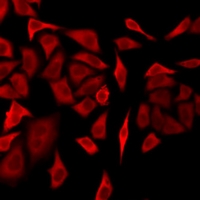

Immunofluorescent analysis of DRP1 staining in U2OS cells. Formalin-fixed cells were permeabilized with 0.1% Triton X-100 in TBS for 5-10 minutes and blocked with 3% BSA-PBS for 30 minutes at room temperature. Cells were probed with the primary antibody in 3% BSA-PBS and incubated overnight at 4 °C in a humidified chamber. Cells were washed with PBST and incubated with a DyLight 594-conjugated secondary antibody (red) in PBS at room temperature in the dark. Immunofluorescent analysis of DRP1 staining in U2OS cells. Formalin-fixed cells were permeabilized with 0.1% Triton X-100 in TBS for 5-10 minutes and blocked with 3% BSA-PBS for 30 minutes at room temperature. Cells were probed with the primary antibody in 3% BSA-PBS and incubated overnight at 4 °C in a humidified chamber. Cells were washed with PBST and incubated with a DyLight 594-conjugated secondary antibody (red) in PBS at room temperature in the dark.